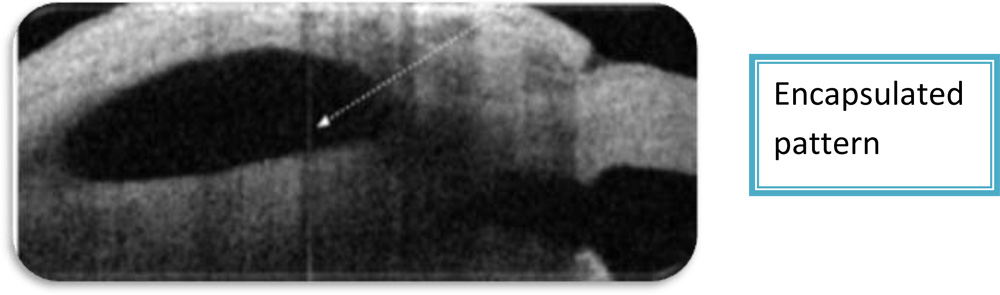

3.Bleb pattern– Three types of bleb patterns were noted-Diffuse, cystic and non functioning.

b) Non functioning blebs/ encapsulated bleb-were characterized by the absence of subconjunctival fluid collection and high intrableb reflectivity.